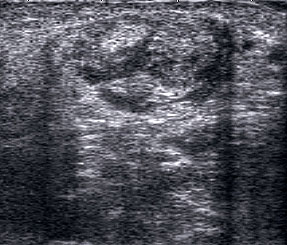

Ganglien imponieren als runde, echofreie Raumforderungen.

Abbildung 9

Lagerung: Rückenlage.

Schnittebene: LS und TS über der Pathologie.

Referenzstrukturen: Reproduzierbare knöcherne Landmarken in Abhängigkeit von der Lokalisation. Befunde: Ganglien finden sich häufig im fibularen Anteil der Gelenkkapsel des oberen Sprunggelenks (Abb. 9), aber auch an den Gelenkspalten und paratendinös im Bereich von Sehnenscheiden streck- oder beugeseitig. Ganglien sind sonographisch als meist runde echofreie Raumforderungen gelenk- oder sehnennah darstellbar.